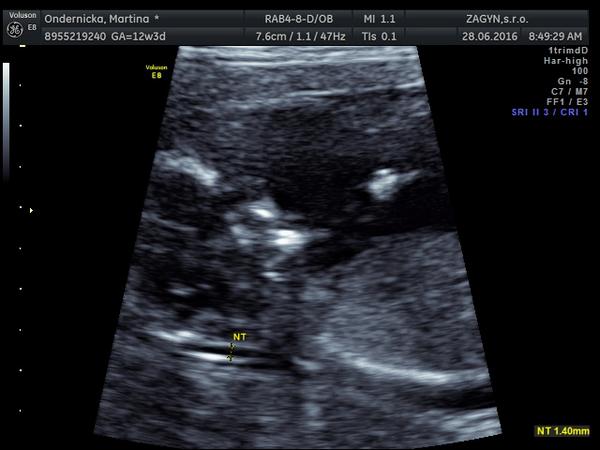

@lessiie to na prvom obrazku - tu bublinku za zatylkom a chrbatikom - to si myslela ze je NT? ...ale to vibec nie je NT, to je proste len blana, v ktorej je babo obalene😊 To NT je aj na prvej foto uplne ok😊 Mna takto vystrasili tiez, presne takto isto som to mala aj ja, hned mi teda spravil kontrolne sono na kvalitnejsim ultrazvuku a skonstatoval, ze to je len blana, ale na menej kvslitnom uzv to moze vyzerat ako NT a potom vznikaju zbytocne stresy...😊

@xarona verim ze to bude v poriadku😊 ...popravde, z tvojho obrazku si netrufam povedat, ci to je len blana ci NT, matie ma to, ze je tam ten "kopcek", ale kludne to moze byt aj ta blana😊

Tu su 2 obrazky z netu - na oboch vidno aj tu blanu aj NT...niektori dr vsak mylne povazuju za NT prave tu blanu...verim ze to bude aj tvoj pripad😊